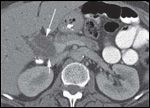

DR. PAUL RUSS: The initial CT scan of the abdomen with intravenous and oral contrast revealed a 2.7-cm, hypodense, hypovascular, solid mass in the head of the pancreas and also involving the uncinate process. In addition, there was dilatation of the pancreatic, intrahepatic and extrahepatic ducts without any evidence of distant metastatic or lymph node involvement. However, the second CT scan done, at the time of her clinic visit, showed post-surgical changes with an ill-defined soft tissue mass in the operative bed. There were also five new hypodense lesions in the liver, with the largest lesion in the anterior segment measuring 1.3 × 1.5 cm. There were two lesions in the dome, measuring 1.1 cm and 8 mm, along with two additional subcentimeter lesions in the right lobe (Figures 1A-1D, 2).

DR. PAUL RUSS: Because pancreatic adenocarcinoma is typically hypovascular compared to background pancreas and liver, the primary neoplasm is depicted as hypodense to the pancreas, and metastases as hypodense to the liver. However, some pancreatic adenocarcinomas remain occult, even with the use of advanced CT techniques, and in those cases the diagnosis can sometimes be surmised by using indirect, secondary signs like pancreatic and/or bile duct dilatation, and post-obstructive pancreatic atrophy. In this case, we see one of the typical hypodense lesions consistent with metastatic pancreatic cancer.